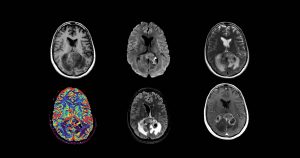

Chimiothérapies dans les tumeurs cérébrales

Les données des études récentes, cliniques ou translationnelles, nous ont donné d’importantes clés pour construire les études cliniques actuelles. La classification OMS des tumeurs du système nerveux central a intégré…